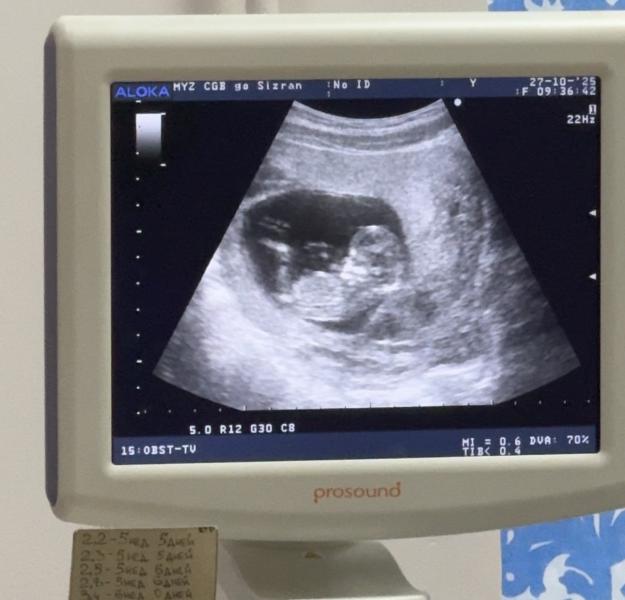

Поставили гематому 3 см. Но все окей.

Все хорошо, срок ставят 12.5.